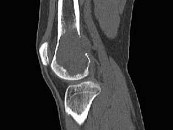

- 单项选择题女,38岁, 因右大腿远端部有疼痛,可摸到肿块, 结合图像,最可能的诊断是 ( )

E、骨巨细胞瘤